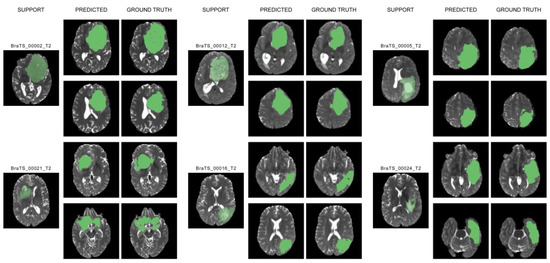

5. Results and Discussion